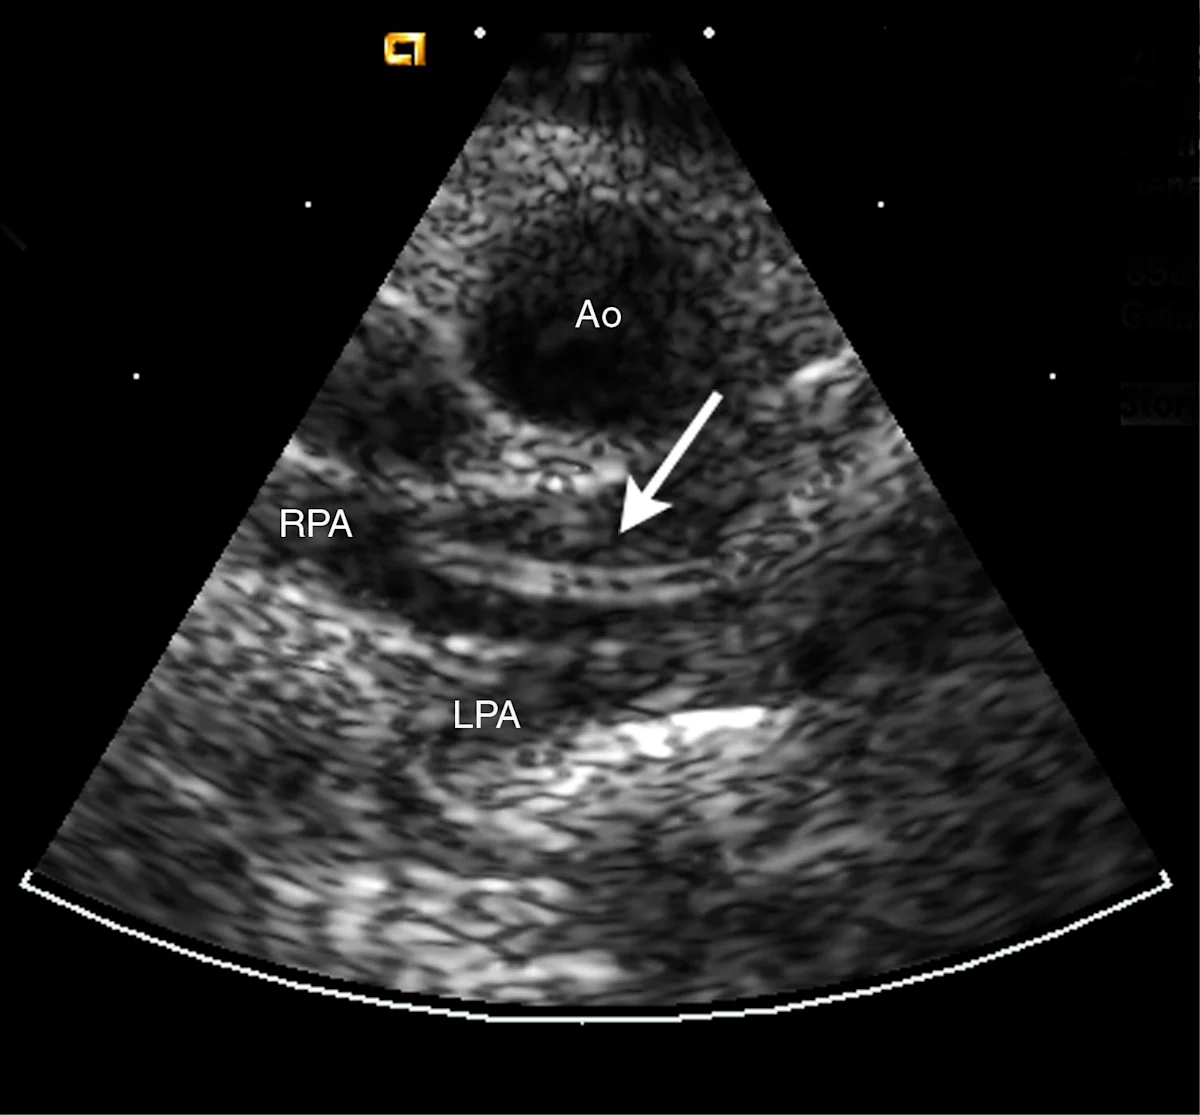

Echocardiographic FindingsRight ventricular hypertrophy may be observed but the echocardiogram is most often normal. Adult heartworms, observed as double-walled (railroad track) echoes (Figure 5) are seen most often in main, right, and left pulmonary arteries, but also in the right ventricle and atrium.

A short-axis, 2-dimensional echocardiogram obtained from an 18-year-old castrated male, feline cancer patient with a cardiac murmur. An adult heartworm can be identified as 2 echo-dense parallel lines in the right pulmonary artery (arrow).

Ao=aorta; RPA=right pulmonary artery; LPA=left pulmonary artery